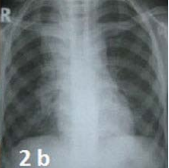

Laboratory reports revealed anemia; Mantoux test was reactive (18×15mm). Chest X ray was suggestive of mediastinal lymphadenopathy. Skin biopsy confirmed the diagnosis of LS and the child was started on 4 drugs ATT from DOTS centre. After four weeks of ATT, the girl was asymptomatic and skin lesions disappeared completely.

Chest X-ray shows enlarged lobulated lymph nodes in right paratracheal, tracheobronchial and hilar region with multiple small nodular shadows (miliary) diffusely scattered in bilateral lung parenchyma suggestive of pulmonary tuberculosis.

Figure 2b: Chest X-ray shows enlarged lobulated lymph nodes in right paratracheal, tracheobronchial and hilar region with multiple small nodular shadows (miliary) diffusely scattered in bilateral lung parenchyma suggestive of pulmonary tuberculosis.